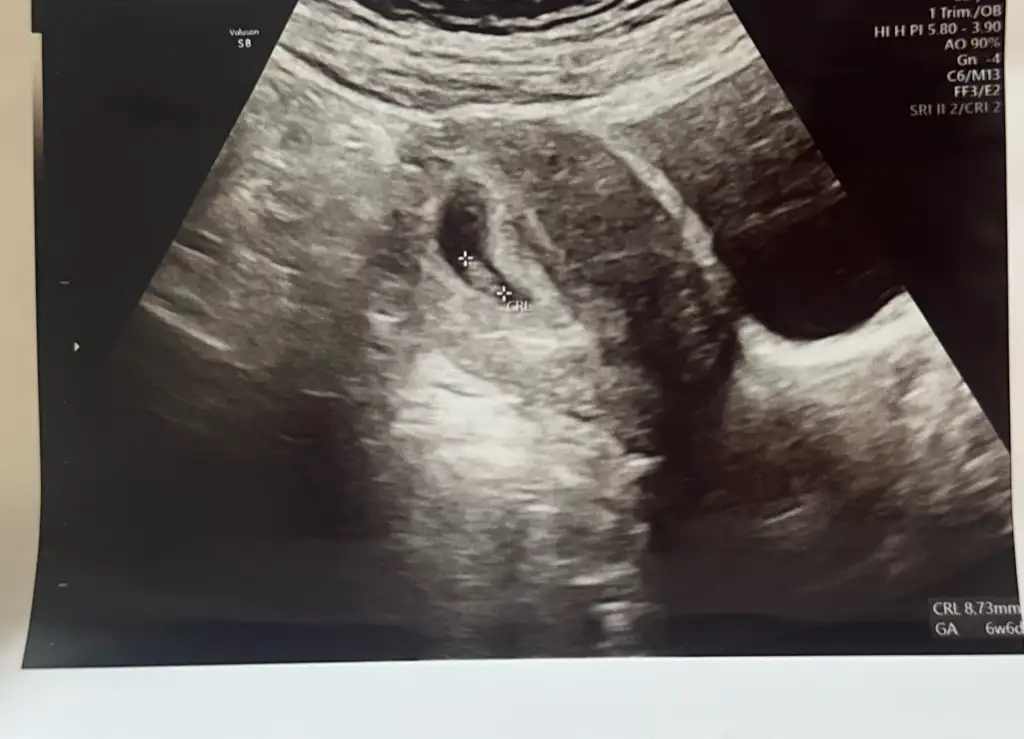

Hiç belirtim yoktu göğüs hassasiyeti haricinde heralde oluşmadı diye korka korka gittim doktora ama çok şükür kalbide yeni atmaya başlamış azda olsa duyabildik 6+6

Erkek bebek kesesi fasulye gibi derler, doğru mu acaba sizinle takip edelim bakalım doğru muymuş. Kesesi çok net naşallahHiç belirtim yoktu göğüs hassasiyeti haricinde heralde oluşmadı diye korka korka gittim doktora ama çok şükür kalbide yeni atmaya başlamış azda olsa duyabildik 6+6Eki Görüntüle 3619184